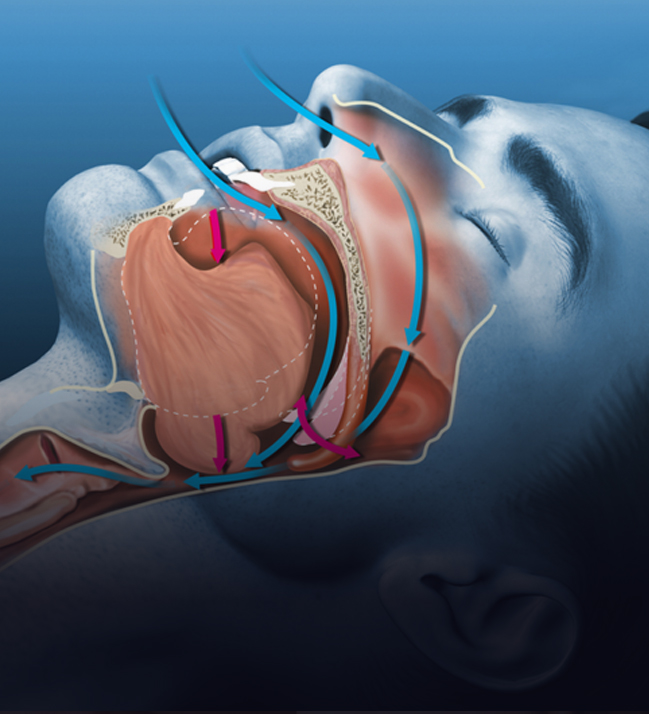

Uyku Apnesi

Uyku Apnesi Cerrahisi